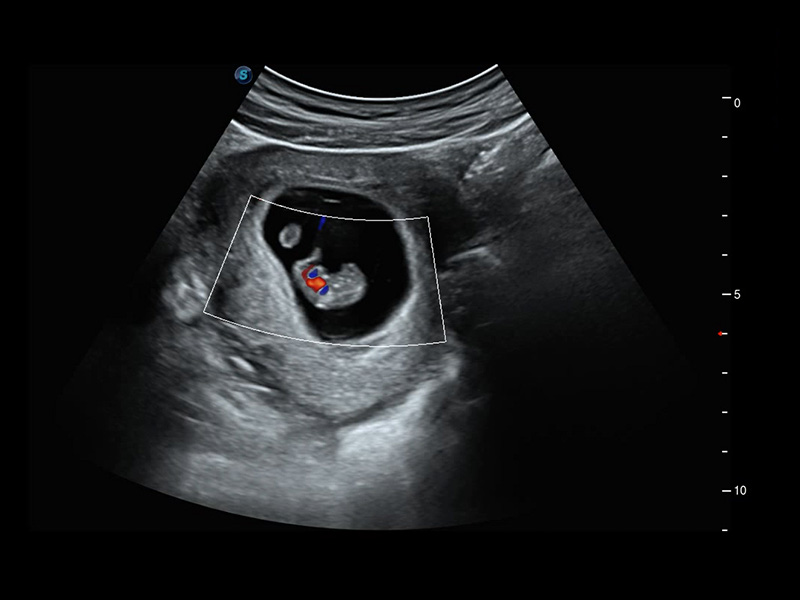

S-Fetus*

S-Fetus è uno strumento di facile utilizzo che consente il rilevamento completamente automatico e preciso dei piani più significativi e delle misurazioni della biometria fetale, utilizzate frequentemente. Con la modalità cine-loop della testa del feto, S-Fetus è in grado di estrarre i piani standard e visualizzare i risultati della misurazione in un secondo, riducendo notevolmente Il numero di battute e i tempi di lavoro necessari. È progettato per trasformare gli esami ecografici ostetrici in un'esperienza molto più comoda, veloce e piacevole.

1 OFD(HC): 87,03 mm

HC: 251,00 mm

GA: 27w 1d

HC/AC: 96,13%

2 BPD: 70,56 mm

GA: 28 w 2d

S-Fetus(acq.)

& S-Fetus(meas.)